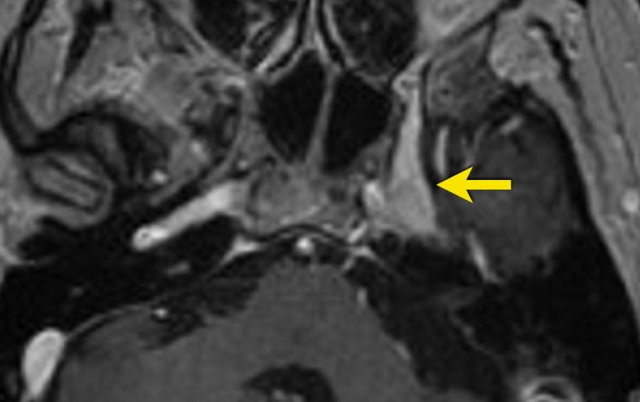

67- year old female with a history of breast cancer with metastases to bone and liver. She presents with numbness on the left side of her face.

Axial 2D FLAIR show an asymmetric cavernous sinus, with dural thickening on the left.

Post-contrast imaging shows increased enhancement of the left side of the cavernous sinus, extending into Meckel’s cave.

Suspicious for metastasis of breast carcinoma.